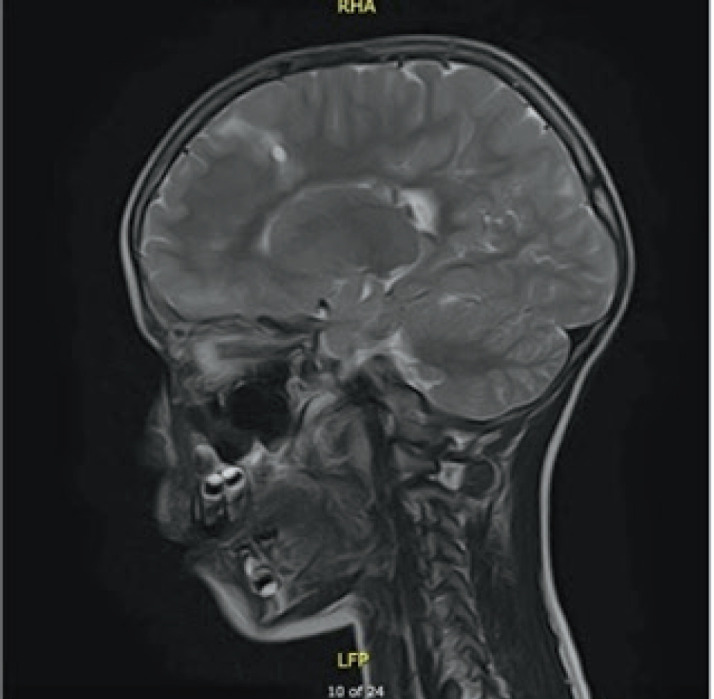

Case presentation: In this case report, we describe a seven year old patient with the clinical manifestation of TSC that includes supratentorial changes, subependymal hamartomas and angifibromas in the facial area. Besides the brain and skin changes, no other TSC characteristics were observed. The patient was referred to molecular genetic testing using Next Generation Sequencing (NGS). Results: Clinical exome sequencing revealed intronic TSC2 c.4849+2T>G variant. The variant was confirmed using Sanger sequencing on the subject. However, the variant was not detected in the parents, which indicated that it arose de-novo. The RegSNP-intron, Mutation Taster and Human Splicing Finder were used as a bioinformatic tools to predict the possible effect on protein. Using bioinformatic tools, it was determined that the variant is possibly damaging to protein.